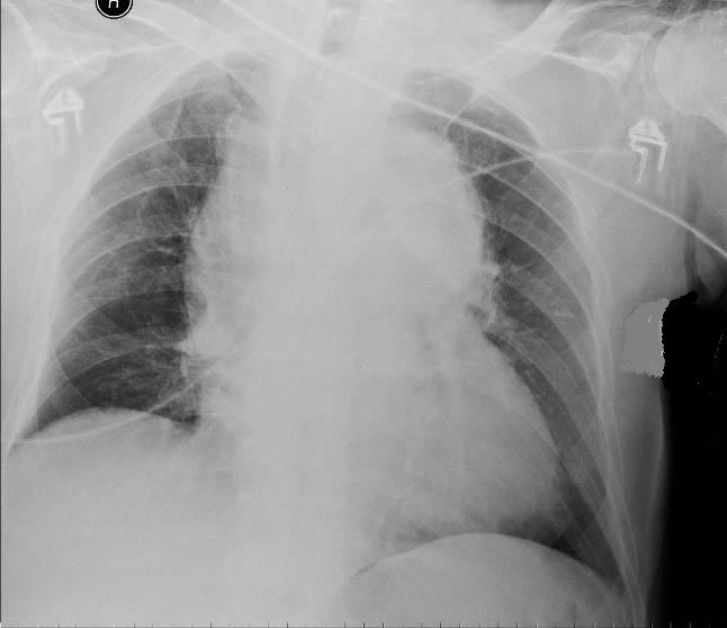

What is shown here? (2)

Borderline cardiomegaly

Widened mediastinum

Due to arotic dissection.

Consider CT if uncertain.